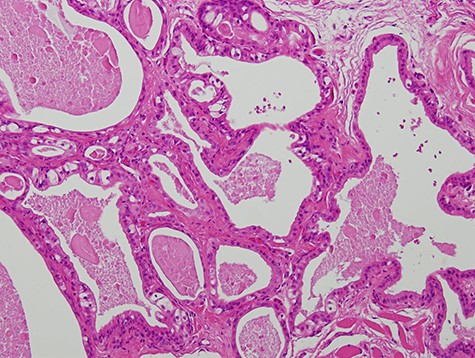

A 63-year-old man was referred to our hospital for treatment of a nodule on his tongue in May 2003. His medical history included Wolff–Parkinson–White syndrome and atrial fibrillation, both of which were controlled adequately by his primary care physician. Physical examination revealed very slight swelling at the right edge of his tongue. The patient reported some spontaneous pain. It was diagnosed as inflammation of the foliate papilla; the patient was followed-up with a gargle prescription. In September 2005, an elastic soft mass, 4 mm in diameter, was observed along the right edge of his tongue (Fig. 1). It was clinically diagnosed as a benign tumour and removed under local anaesthesia. Microscopically, the lesion was composed of multiple cysts of various sizes and shapes, with or without papillary intraluminal short projections (Fig. 2). Many cyst cavities contained eosinophilic fluid. The lesion was well-delineated, but the capsular structure was ill-defined. The stroma was fibrous connective tissue without lymphocytic components. The cystic cavities were lined by a bilayered epithelium composed of luminal columnar cells and basal cuboidal cells. Both luminal and basal epithelial cells were eosinophilic; some clear cells were seen (Fig. 3). Mitotic figures and cellular atypia of epithelial cells were not seen. Immunohistochemically, both luminal and basal cells were CAM5.2+, basal cells were p63+, apical half of the luminal cells were 34βE12+, and the liminal surface was CEA+. The specimen was diagnosed as cystadenoma, based on the histopathological findings.

Micrograph showing the lesion composed of multiple cysts of various sizes and shapes (haematoxylin–eosin stain, 100×).

Micrograph showing the cystic cavities lined by a bilayered epithelium (haematoxylin–eosin stain, 200×).